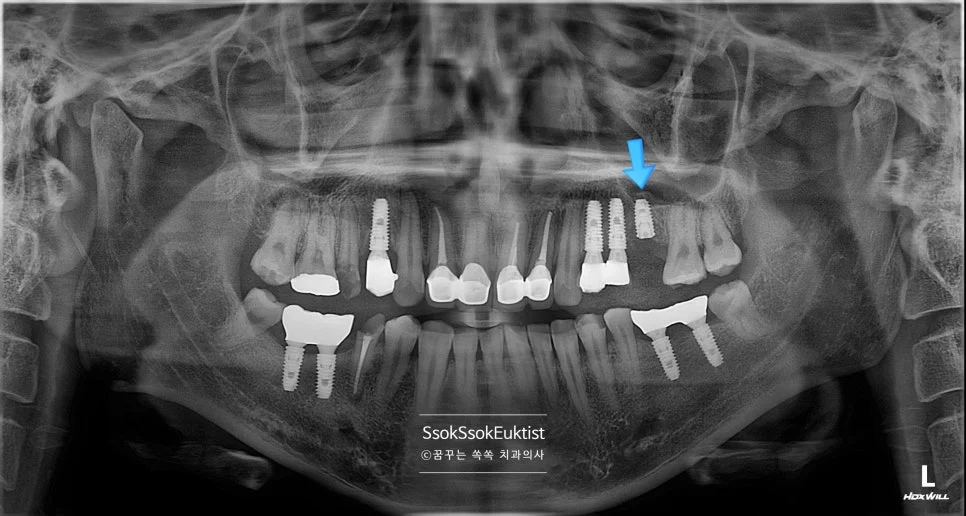

2차 수면 마취 — 우측 임플란트 3개 식립 완료 (화살표)

가능한 주변 골보다 2~3mm 깊게 임플란트가 온전히 뼈 안에 잠기게 식립되었다면 잘 심긴 임플란트입니다.

오른쪽은 뼈이식이 많이 들어갔기에 3달의 치유 기간을 가집니다.